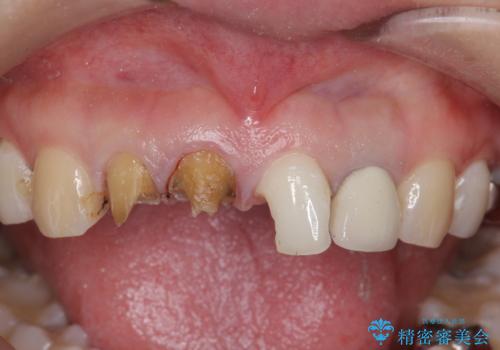

- 前歯を天然の歯のようにきれいにやりかえたいと希望され来院されました。

根尖病変の存在が判明したため、感染根管治療後にオールセラミックジルコニアクラウンを製作します。

- 37万円(仮歯×3・ファイバーコア×2・ジルコニアクラウン×3)費用は治療当時の料金となります